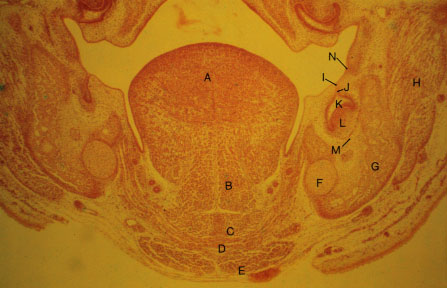

- K-slide 8: Higher magnification of slide 7

- A. Tongue

- B. [Genioglossus]

- C. [Geniohyoid]

- D. [Mylohyoid]

- E. [Anterior belly of digastric]

- F. Meckel's cartilage

- G. Developing mandibular bone

- H. Buccinator muscle

- I. Dental lamina

- J. Deciduous dental lamina

- K. Enamel organ

- L. Dental papilla

- M. Dental follicle

- N. Mandibular vestibular lamina